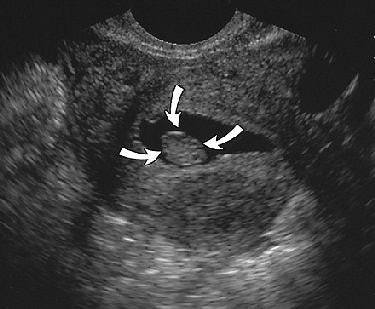

![]() |

| Same patient as above. Sonogram obtained after saline infusion shows homogeneous echogenic mass (arrows) in endometrial cavity, and no submucosal involvement by posterior uterine leiomyoma is present. Laifer-Narin S, Ragavendra N, Parmenter EK, Grant EG, "False-Normal Appearance of the Endometrium on Conventional Sonography: Comparison with Saline Hysterosonography," (AJR 2002; 178:129-133). |